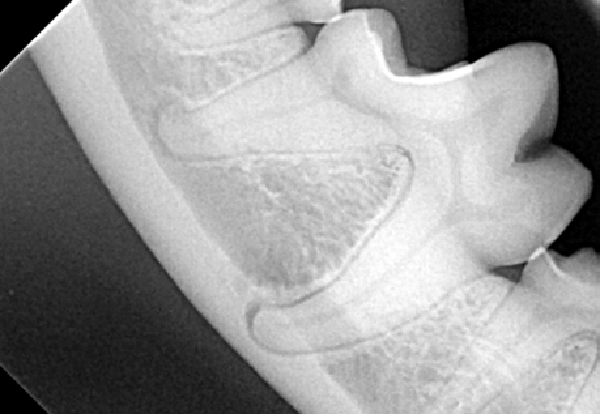

Figure 1A : Radiographie intra-orale de la première molaire mandibulaire droite d’un chien bichon de 6kg. L’examen radiographique est normal, il montre l’importance de l’espace occupé par les racines dentaire au sein de la mandibule chez un chien de petite taille.